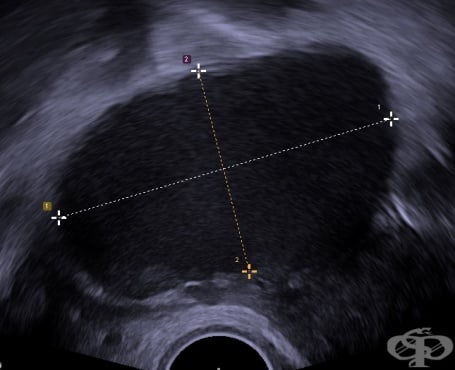

Ендометриоза Ендометриоза Симптоми на ендометриоза Симптоми на ендометриоза Ендометриоза Стадий 1 Стадий 2 Стадий 3 Стадий 4 Ехография - шоколадова киста (ендометриома) Лапароскопия на ендометриоза Лапароскопия на ендометриоза Хиатологично изследване на ендометриоза Ендометриоза на десния яйчник Аденомиоза на матката Ендометриоза и аденомиоза

ЕндометриозаЕндометриозаСимптоми на ендометриозаСимптоми на ендометриозаЕндометриозаСтадий 1Стадий 2Стадий 3Стадий 4Ехография - шоколадова киста (ендометриома)Лапароскопия на ендометриозаЛапароскопия на ендометриозаХиатологично изследване на ендометриозаЕндометриоза на десния яйчникАденомиоза на маткатаЕндометриоза и аденомиоза Ендометриоза